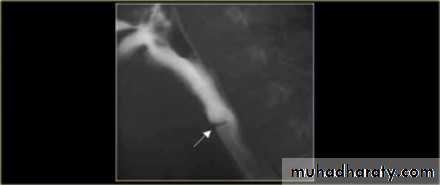

Webs

Majority protrude from anterior esophageal wall

short, thin web (arrows) with minimal intraluminal extension.